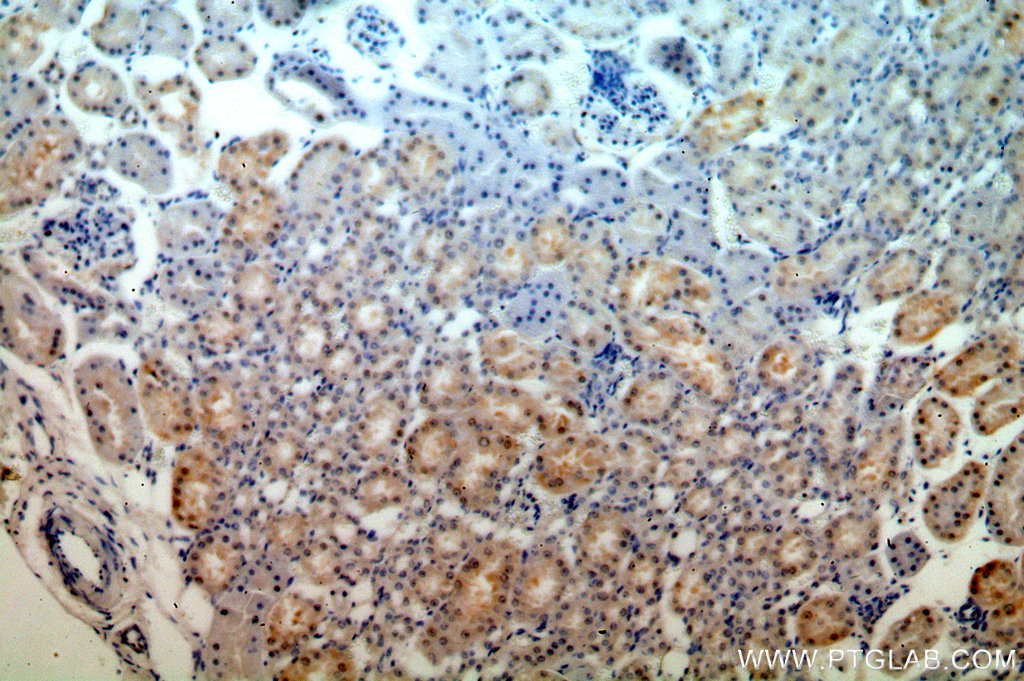

| Positive IHC detected in | human kidney tissue Note: suggested antigen retrieval with TE buffer pH 9.0; (*) Alternatively, antigen retrieval may be performed with citrate buffer pH 6.0 |

| Immunohistochemistry (IHC) | IHC : 1:20-1:200 |